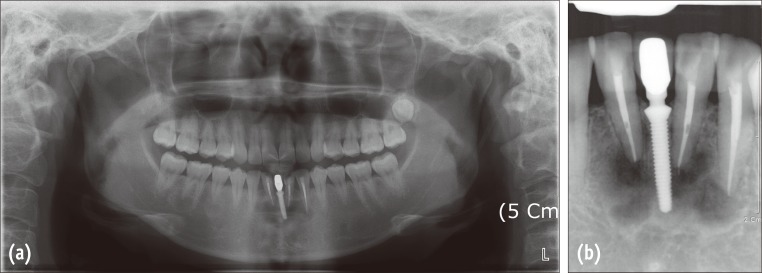

Panoramic and periapical radiographs obtained at the initial visit (after the patient referral) showed mixed radiolucent and radiopaque areas in the mandibular anterior region (#32, 33, 42 and the implant between 32 and 42) and multiple radiolucent areas on the right lower posterior teeth (Figure 2).

The patient visited the hospital without an appointment 21 months after the biopsy because of discomfort in the mandibular anterior vestibule. Her chief complaint was pain on palpation, which had started 2 days prior to her visit. No signs of infection were detected. Cone-beam CT (CBCT, Pax-Zenith3D, Vatech, Hwaseong, Korea, 104 Kvp, 5.5 mA) radiograph was taken to assess any changes in lesion size and development (Figure 5). Based on CBCT views, the apical lesions of madibular anterior teeth and the implant appeared to become more radiopaque. The patient was requested to return if she exhibited any signs of fever, swelling or pain. She did not experience any discomfort after the emergency visit. The patient was instructed to maintain annual routine check-ups.

Figure 2

Radiographic examinations performed at the initial visit (in April, 2009) of the patient. (a) A panoramic radiograph showing multiple mixed radiopaque and radiolucent areas at the apices of the mandibular teeth; (b) A periapical radiograph of the lower anterior teeth. Two incisors and left canine were endodontically treated and an implant was included in the apical lesion.

Figure 5

Radiographic examinations performed in 2011. A panoramic reconstructed image of cone-beam computed tomography (CBCT) obtained in September, 2011 (21 months after the biopsy).

Figure 2 Radiographic examinations performed at the initial visit (in April, 2009) of the patient. (a) A panoramic radiograph showing multiple mixed radiopaque and radiolucent areas at the apices of the mandibular teeth; (b) A periapical radiograph of the lower anterior teeth. Two incisors and left canine were endodontically treated and an implant was included in the apical lesion.